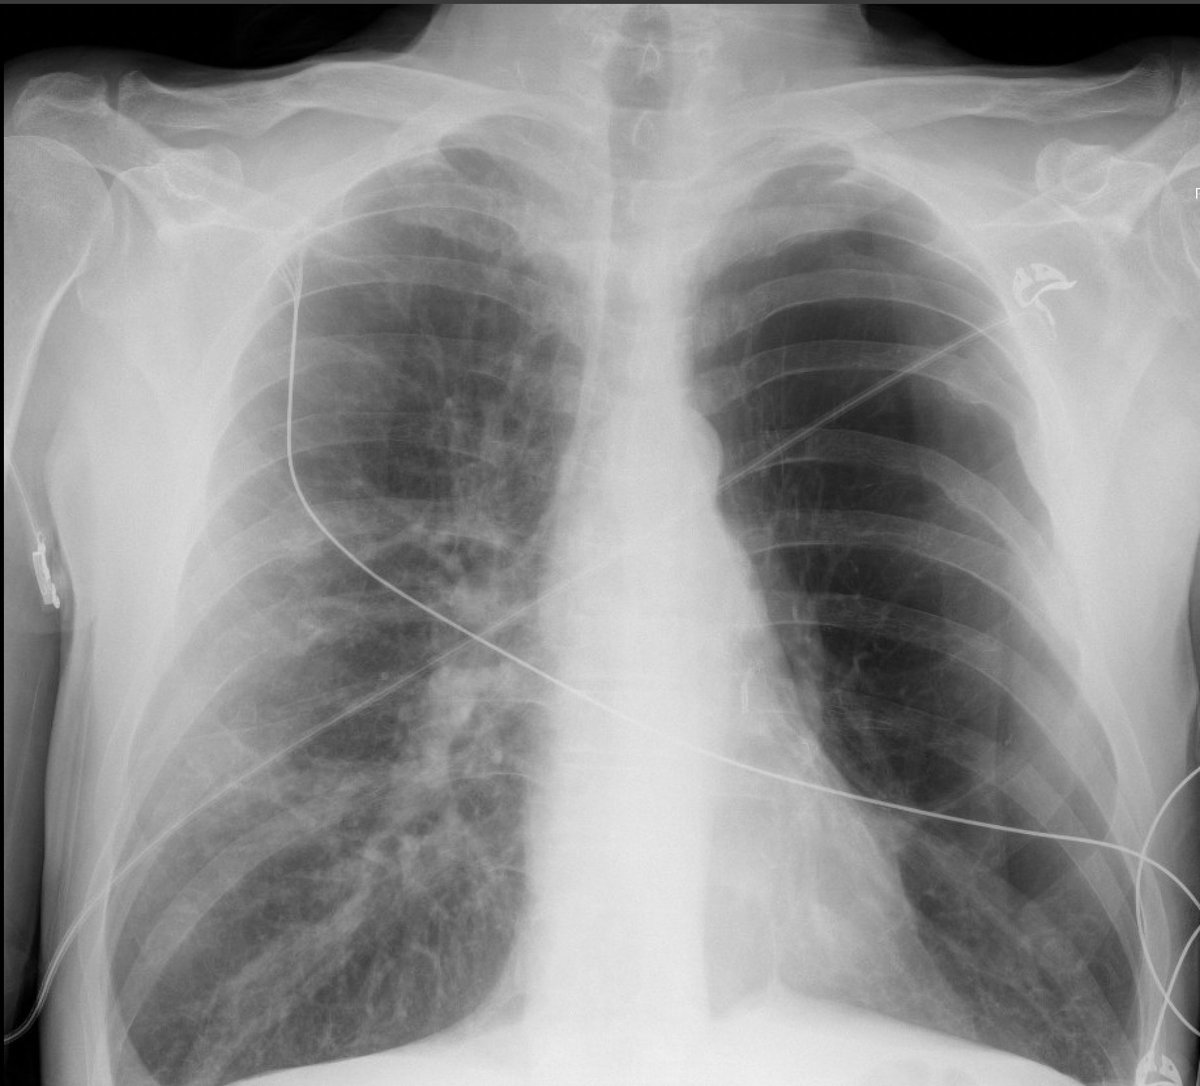

you're managing a new admission who is relatively undifferentiated (presenting with hypotension, hypoxemia, and altered mental status). the radiology tech wheels out of the room and shows you this film. what is your next move? (#1/4)

this is actually a skin fold, not a pneumothorax. there are several hints of this on the chest X-ray, but the safest (most idiot-proof) way to sort it out is lung ultrasonography. lung slide on POCUS at several locations on the left chest confidently & immediately excluded PTX😃

key points:

🫁STAT calls from radiology about "pneumothorax" often turn out to be skin folds

🫁unless the PTX is unequivocal & the patient is crashing (e.g., definite tension PTX), *always* do POCUS before placing a chest tube

🫁for PTX diagnosis, POCUS eats x-ray for lunch